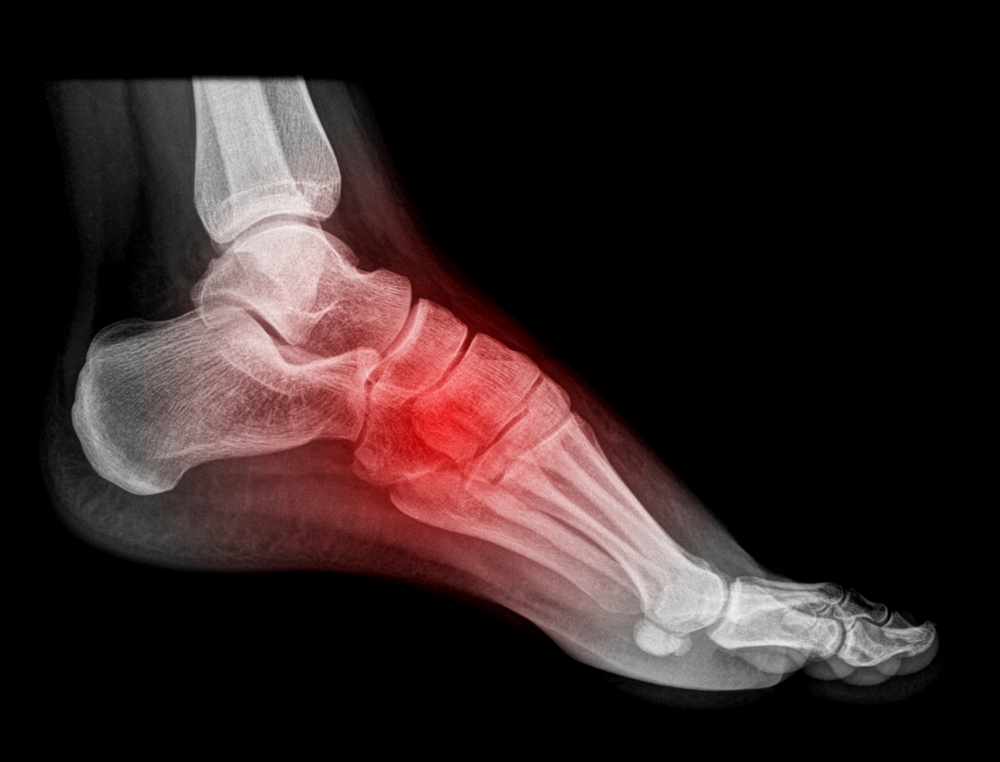

Arthritis Foot Pain Management . A person can discuss their. Here’s how to manage symptoms. Foot arthritis causes pain, stiffness, and swelling that can reduce mobility and quality of life. Arthritis can cause pain and stiffness in any joint in the body, and is common in the small joints of the foot and ankle. How to heal arthritis foot pain. There is no cure for arthritis, but there are a number of treatments that may help. Medications to ease pain and inflammation, slow bone loss, slow disease progress or prevent joint damage are important in treating. A person may find that exercise, combined with weight loss if necessary, pain management, and lifestyle changes, alleviates pain and stiffness. Learn about the causes, exercises and treatments as well as the structure. Now that we’ve established why your feet are hurting, consider these strategies for easing the pain,. Our feet and ankles are complex so they can be prone to arthritis or pain.